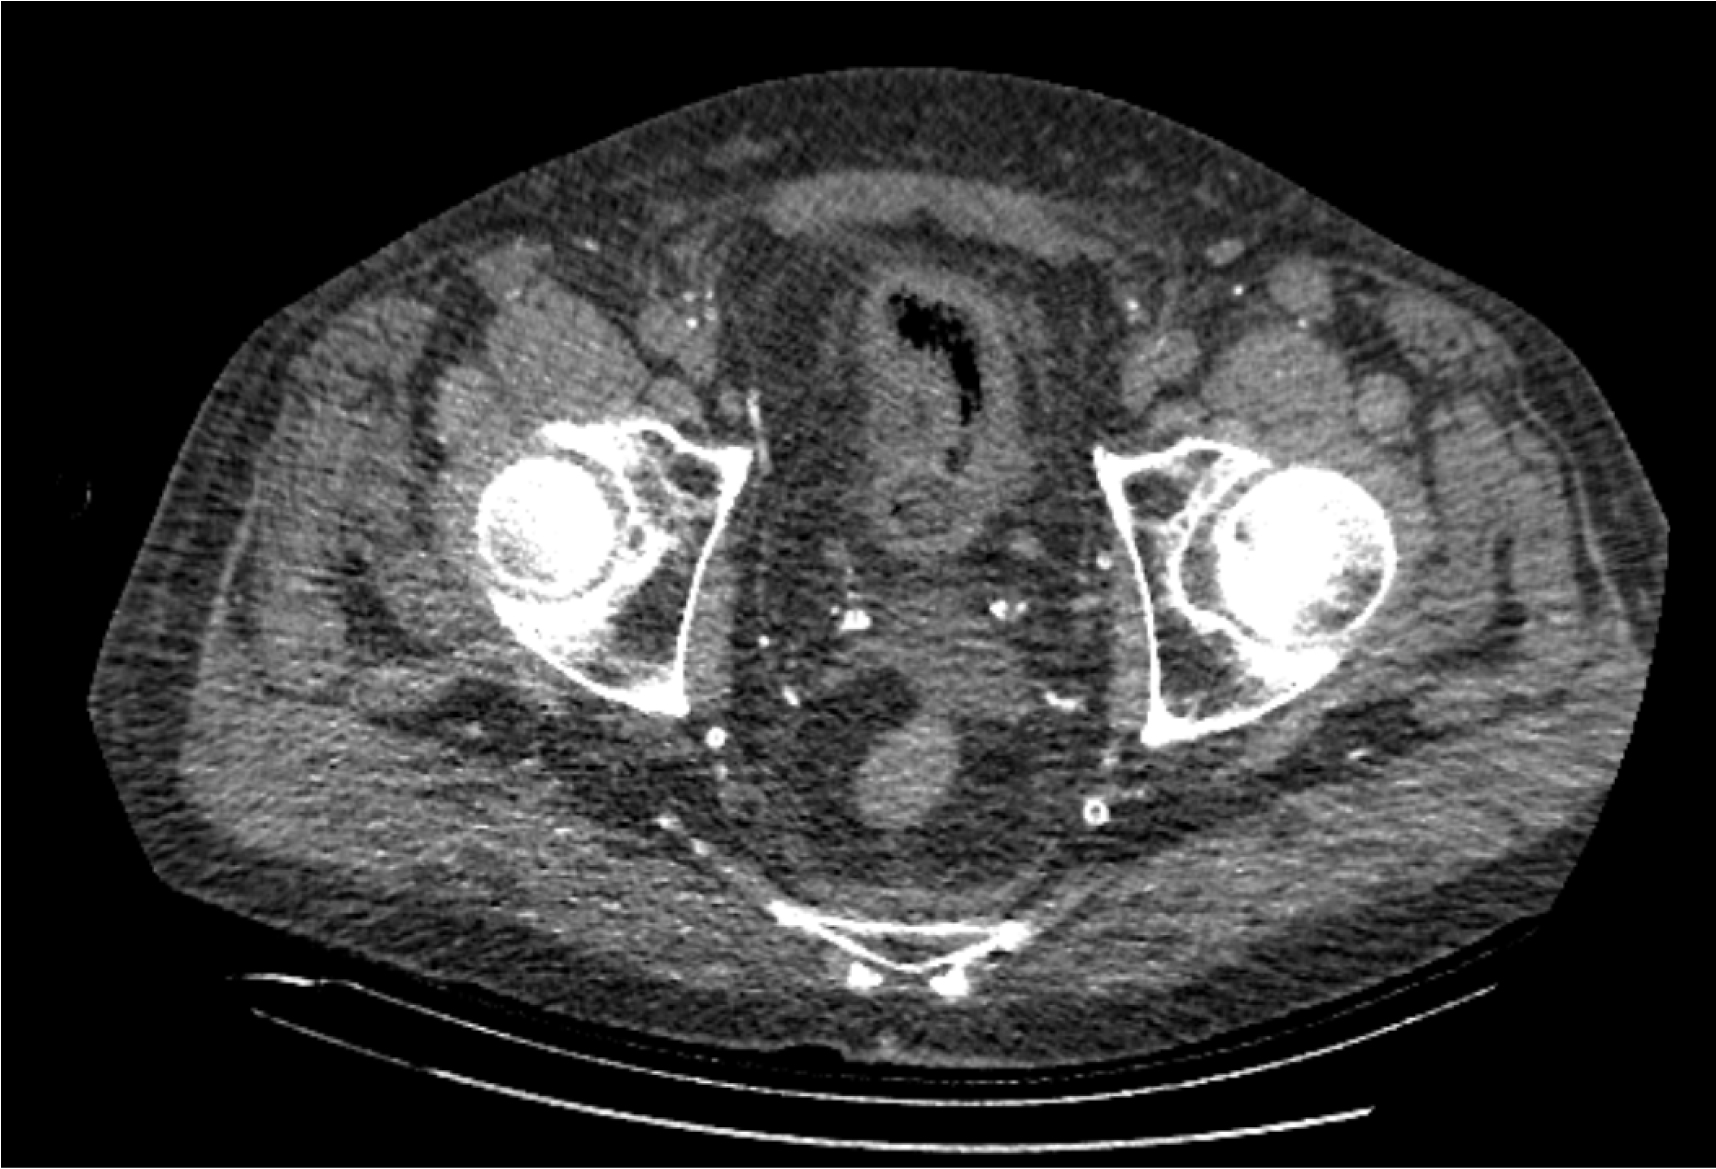

На следующий день состояние пациента оставалось тяжелым, с отрицательной динамикой, креатинин сыворотки возрос до 735,2 ммоль/л, Появились жалобы на слабость, тошноту. При осмотре: живот мягкий, вздут по всем отделам, при пальпации болезненный. Область почек не изменена, при пальпации безболезненна, патологических изменений в области почек не выявлено. Симптом поколачивания отрицательный билатерально. При УЗИ были обнаружены плевральный выпот по 300–400 мл с каждой стороны, гепатомегалия, увеличение размеров селезенки, асцит. Кроме того, в обеих почках были визуализированы тени, характерные для конкрементов. По данным компьютерной томографии (КТ) конкрементов не обнаружено, но в лоханке, на всем протяжении левого мочеточника и, частично, в правом мочеточнике, а также в мочевом пузыре визуализировался газ (рис. 1–6).

Рис. 1. Компьютерная томография органов брюшной полости, забрюшинного пространства, органов малого таза. Газ в мочевом пузыре

Рис. 2. Компьютерная томография органов брюшной полости, забрюшинного пространства, органов малого таза. Газ в мочевом пузыре